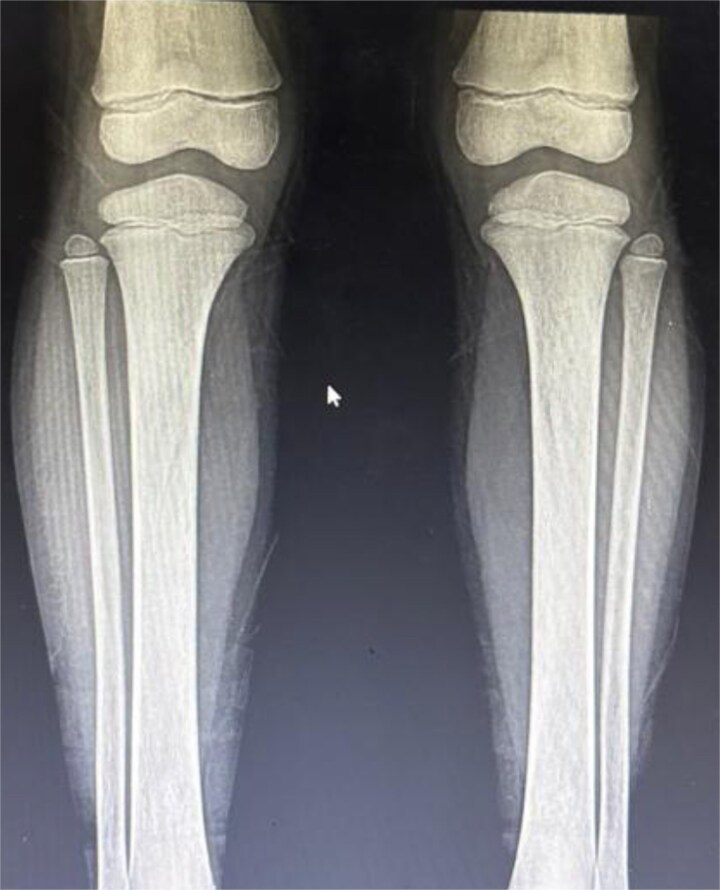

朗格汉斯细胞组织细胞增生症(LCH)是一种罕见的疾病,朗格汉斯细胞浸润到各种器官,导致组织损伤。本病例描述一名确诊为LCH的6岁男性,其表现为疲劳、过度口渴、多尿和不明原因的体重增加等症状恶化。x线检查显示颅骨和长骨有广泛的溶骨性病变,符合LCH。此外,通过激素检测和影像学证实,患者出现明显的内分泌功能障碍,包括甲状腺功能减退、尿崩症和肾上腺功能不全。该病例强调了在LCH患者中考虑内分泌功能障碍的重要性,并强调了多学科方法在管理复杂病例中的作用。激素替代治疗,以及LCH的化疗开始,患者表现出临床改善。

Langerhans cell histiocytosis (LCH) is a rare disorder in which Langerhans cells infiltrate various organs, causing damage to tissues. This case describes a 6-year-old male diagnosed with LCH, who presented with worsening symptoms of fatigue, excessive thirst, polyuria, and unexplained weight gain. Radiographic findings revealed extensive osteolytic lesions in the skull and long bones, consistent with LCH. Additionally, the patient developed significant endocrine dysfunction, including hypothyroidism, diabetes insipidus, and adrenal insufficiency, as confirmed through hormonal assays and imaging. The case emphasizes the importance of considering endocrine dysfunction in patients with LCH and underscores the role of a multidisciplinary approach in managing complex cases. Hormonal replacement therapy, along with chemotherapy for LCH, was initiated, and the patient showed clinical improvement.